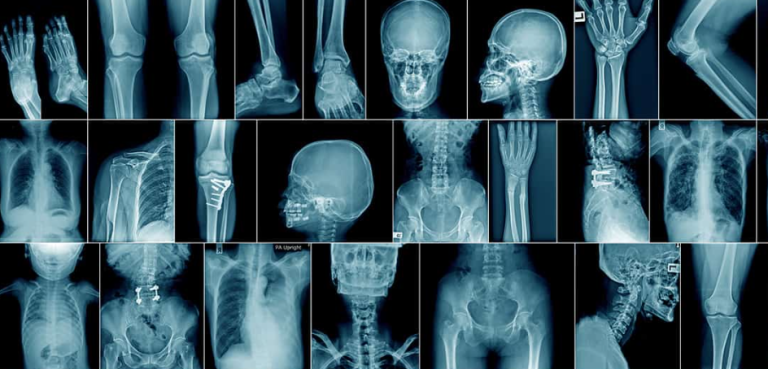

• Radioloģijas izmantošanas integrēšana fizioterapeita praksē: ievads fizioterapeitiem

27.09.25 notikušo vebināru vadīja Edward Proctor  praktizējošs radiologs no Lielbritānijas, ar vairāk…